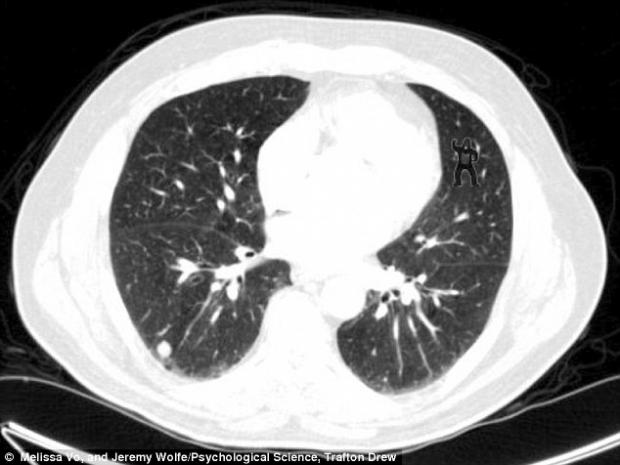

Un studiu psihologic condus de cercetătorii unui spital din SUA a arătat că peste 83% dintre radiologi nu au văzut gorila care apare în imaginea de mai jos. Şi asta cu toate că au privit-o în mod insistent şi repetat.

Testul gorilei a fost realizat cu ajutorul a 24 de radiologi care au fost rugaţi să examineze radiografiile a cinci pacienţi (4 sănătoşi şi unul care suferea de cancer la plămâni), arată Daily Mail.

Primele patru radiografii aparţineau persoanelor sănătoase. Gorila era „ascunsă” în 5 imagini consecutive dintr-un calup de 239 de imagini cu radiografii ale persoanei bolnave.